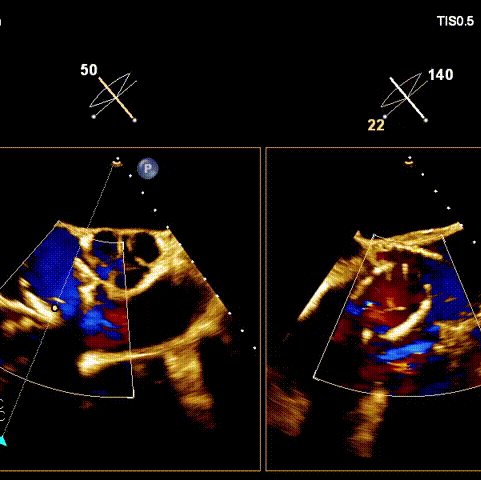

術(shù)后超聲

術(shù)前經(jīng)過全面系統(tǒng)的評估后,考慮患者存在高齡、心功能減低、三尖瓣瓣環(huán)重度擴張(三尖瓣極重度反流)等高危因素,因此廈心結(jié)構(gòu)心團隊聯(lián)合超聲心動、麻醉及護理團隊,制定了詳盡的圍術(shù)期治療方案及術(shù)中治療難點預(yù)案。術(shù)中,由王焱院長主刀,在蘇茂龍主任超聲心動團隊的輔助,上海市第一人民醫(yī)院陸方林主任的協(xié)助下,僅用時30分鐘,即順利完成了三尖瓣原位置換的手術(shù)。術(shù)中患者血流動力學(xué)穩(wěn)定,術(shù)后即刻顯示LuX-Valve Plus瓣膜位置良好,固定穩(wěn)定,瓣膜功能正常,無瓣周漏。